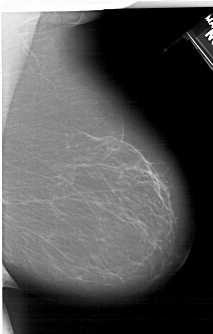

A_1406_1.LEFT_MLO

LEFT_MLO LINES 6136 PIXELS_PER_LINE 4216 BITS_PER_PIXEL 12 RESOLUTION 43.5 OVERLAY